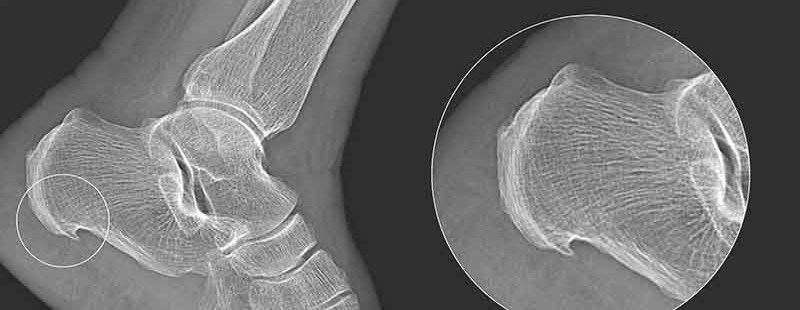

A heel spur develops as a bony protrusion on the calcaneus. It often manifests as sudden and severe heel pain. The formation process of a heel spur typically spans several months and is caused by strain on the muscles and ligaments of the foot, chronic inflammation of the plantar fascia, and repeated tears of the membrane covering the heel bone.

Heel spurs and plantar fasciitis are related conditions but not identical. Plantar fasciitis involves inflammation of the fascia that extends between the heel and the sole of the foot. The inflammation causes intense, stabbing heel pain that may come and go throughout the day. Heel spurs, on the other hand, typically occur as a reaction to chronic plantar fascia inflammation, eventually leading to the formation of additional bony tissue in the form of a spur. Most people do not experience pain directly from a heel spur.